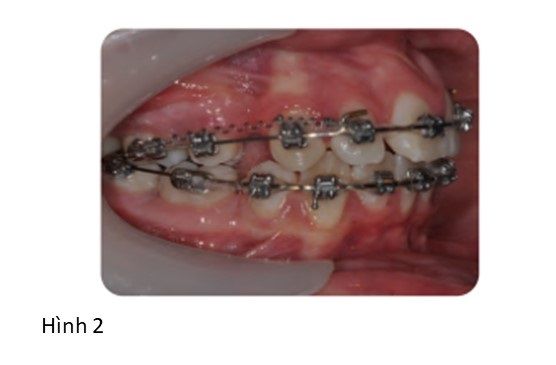

Trong trường hợp này, khí cụ chức năng được sử dụng đầu tiên để giảm độ cắn chìa và sửa chữa tương quan răng hàm. Liệu pháp khí cụ chức năng tiến triển tốt và cả 4 răng hàm nhỏ thứ nhất và răng thứ 3 hàm dưới bên trái sau đó được nhổ bỏ trước giai đoạn điều trị khí cụ cố định (Hình 2).